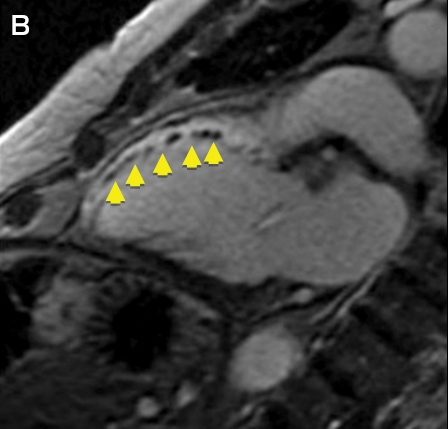

Clinical vignette 3: A 74-year-old man with a late-presentation ST-elevation myocardial infarction is shown to have an occluded left anterior descending artery during coronary angiography. Echocardiography shows an ejection fraction of 40%. Cardiovascular magnetic resonance (CMR) demonstrates that the anterior wall is akinetic, with full thickness infarction and no residual viable myocardium. Based on this information, he does not undergo stenting or coronary artery bypass graft surgery and is treated medically with heart failure therapy.

CMR imaging: two-chamber view showing a dilated left ventricle with akinetic anterior wall (A), and post-contrast imaging showing full thickness infarction of the entire anterior wall with no residual viable myocardium (B, arrows).